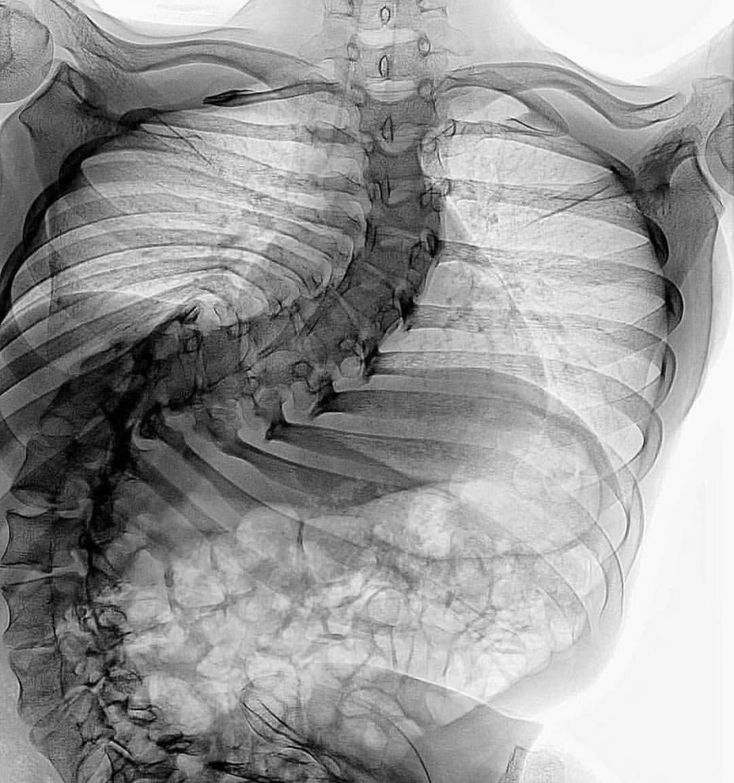

Have you seen a scoliosis like this? 14 year old female with severe scoliosis. The patient underwent multilevel osteotomies and single stage fusion and instrumentation to correct her deformity. In scoliosis, the patient’s spine is curved from side to side or front to back, and may also be rotated. On an x-ray, the spine of an individual with a typical scoliosis may look more like an "S" or a "C" than a straight line. It is quite common in young individuals and is often idiopathic and asymptomatic. In some cases, however, it is the result of underlying structural or neurological abnormalities.